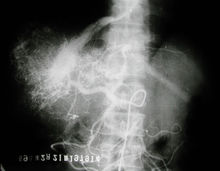

肝臟影像圖

肝臟影像圖肝功能檢驗(yàn)